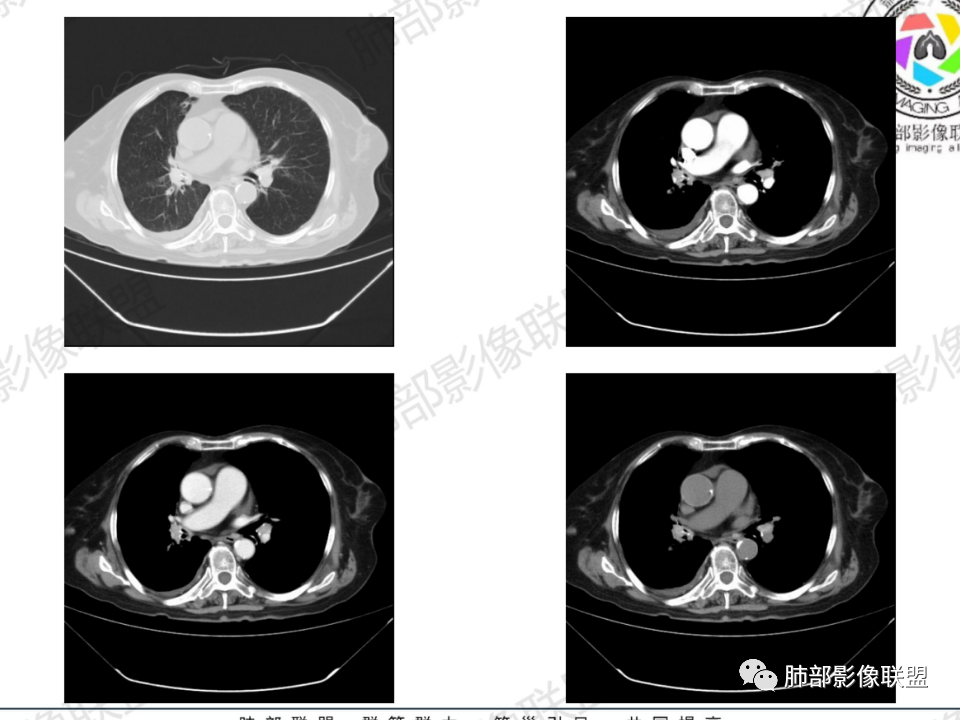

那个人:老年女性,亚急性病程,咳嗽发热。有垂体前叶功能减退,目前激素替代治疗,长期激素,量小,不知道累积量,没有目前激素水平指标。既往有淋巴结结核病史。肿瘤标记物Ca125升高。血沉升高,C反应蛋白轻度异常。影像,右肺上叶靠近肺门团块影,右肺门淋巴结钙化肿大,支气管狭窄,局部增厚,团块影外朝内改变,强化明显,血管破坏不明显,有粘液。和纵隔胸膜分界清楚,周围肺组织有斑片渗出影,右侧胸腔积液,考虑炎性?结核?支气管镜检查除外恶性飞鹰行动:老年患者,影像表现 右肺上叶占位性病变,边界清楚,有分叶征,内见细小钙化,右肺上叶支气管截断,增强病灶不均匀强化,病灶内有条状坏死区(扩张的支气管?),纵膈内未见增大淋巴结,考虑炎性病变,结核可能。一切∮随缘:右肺上叶实性肿块形态不规则,呈三角形,边缘分叶,边界伴有磨玻璃影,近段支气管未见明显显示,可能堵塞,病变平扫密度均匀,增强后可见低密度坏死无强化,周围略强化,右肺下叶散在结节。心包积液,及右侧胸腔积液,临床:有低热,低蛋白血症,肿瘤标记物高,考虑恶性:腺癌,神经内分泌癌(强化偏弱了),淋巴瘤,鉴别:结核红星:老年女性患者右肺上叶,肺门上区 分叶状肿块 ,右肺上叶支气管显示不清,增强扫描肿块,中等程度强化可见小斑片状坏死区,病灶内部可见斑点状钙化灶,病灶周围可见斑片状及小斑点状影,纵膈淋巴结增大,其他区域,胸膜下可见斑点状钙化。考虑肉芽肿性病变,结核的可能性大。老年患者最排除肿瘤性病变腺癌。土娃:右上肺不规则肿块影,边缘分叶,边界磨玻璃影欠清,病灶分叉状,内见点状钙化影及坏死灶,支气管堵塞,病灶增强强化不明显。考虑瘤样结核,鉴别淋巴瘤。张小兵:老年女性,亚急性病程,右肺上叶见不规则肿块,边缘平直凹陷为主,周围GGO边界不清,内见点状钙化及坏死灶,增强持续性渐进强化,右侧少量胸腔积液,双肺门及纵隔肿大淋巴结伴钙化,综合考虑慢性炎症。saf:老年患者,影像表现 右肺上叶占位性病变,边界清楚,有分叶征,增强病灶明显不均匀强化,纵膈内未见增大淋巴结,考虑炎性病变,结核可能。小兜:老年女性,咳嗽喘息一月,发热三天,肿瘤标志物升高,长期激素替代治疗。CT示右肺上叶近肺门不规则实变影,周围伴磨玻璃影,增强持续性渐进强化,内部血管破坏不厉害,内部可见多发条形低密度灶,右侧胸腔可见少量积液,双肺门及纵隔可见钙化淋巴结,考虑为炎性病变,结核可能玫:女,79咳嗽,喘息一月,发热三天入院,右肺上叶不规则形软组织密度肿块影,边界清晰,边缘见分叶及细短毛刺,病灶内见点状钙化影及稍低密度区,病灶边缘呈磨玻璃样改变,增强扫描,病灶呈不均匀性强化,考虑炎性病变,鉴别鳞癌。大雄:老年女性,既往诊断淋巴结结核,提示已治愈,近2年服用激素,诱导结核复燃→发热;纵隔肺门淋巴结肿大钙化,压迫支气管,右肺上中下叶支气管均狭窄→喘息咳嗽;尖段支气管受累闭塞→肺不张、支气管粘液栓;累及胸膜,结核性胸膜炎并胸水→右侧胸痛;实验室,血沉快,CA125高,低蛋白,符合;下一步,支气管镜尖段支气管刷检抗酸染色周太狼:老年女性,亚急性病程,肿瘤标志物升高。CT示右肺上叶尖段不规则肿块影,有分叶、收缩,周围伴磨玻璃影,增强渐进强化,内部可见多发条形低密度灶,右侧胸腔及心包少量积液,纵隔内淋巴结稍增大。倾向于恶性病变,肺癌伴阻塞性炎变可能。丽:老年女性,右肺上叶不规则软组织肿块,边缘清晰,内密度不均,可见点状钙化及粘液栓,周围可见片状高密度影,增强后均匀强化,内多发低密度,纵膈多发钙化淋巴结,考虑结核可能大,建议结合支气管镜检查除外肿瘤宇宙:右胸廓缩小,右肺上叶团块影及不张,平直边,周围磨玻璃影,纤细胸膜牵拉,上叶尖段支气管堵塞,明显延迟强化,可见支气管粘液栓,两肺门钙化淋巴结,右侧胸水,考性炎性肉芽肿,鉴别腺癌王秀仙:右肺上叶肺门区肿块,上叶支气管开口阻塞,形态不规则,密度不均,内可见支气管粘液栓及多发小灶性坏死,周围磨玻璃影边缘模糊,渐进强化,右侧胸腔积液、胸膜钙化,考虑炎性肉芽肿性病变,慢性炎症。鉴别鳞癌,结核。刘丹:老年女性,右肺上叶肿块伴钙化,右肺上叶支气管截断,增强后均匀强化,周边可见点片状模糊影,右侧胸腔积液,右肺门淋巴结增大,考虑占位并阻塞性炎症,肿瘤?结核?建议纤支镜检查。小飞:右肺上叶纵隔旁软组织肿块,边缘深分叶、长毛刺及毛刷样短毛刺,边缘磨玻璃影,磨玻璃边界模糊,支气管截断,平扫密度不均,可见点状钙化,增强不均匀明显强化,心影增大,心包积液,右侧胸腔积液,考虑恶性肿瘤,腺癌?秦化君:右肺上叶不规则分叶软组织密度肿块,边缘清晰,胸膜牵拉,周围花花草草,上叶尖段支气管阻塞,内可见点状钙化,增强后密度不均可见支气管粘液栓及坏死区,内见血管分枝。中间段及中叶,下叶支气管狭窄,壁见钙化。右肺门淋巴结肿大,右侧胸腔积液,心包粘连肥厚。考虑1右上肺恶性病变,鳞癌?2右肺多叶段支气管狭窄,考虑支气管内膜结核?3胸腔积液及肺门淋巴结肿大,转移?风儿:老年女性,右肺上叶肿块,形态不规则,外围大内带小,边缘分叶膨隆平直及毛糙,密度不均,内见支气管粘液栓及多发小灶性坏死,坏死边缘清晰 ,渐进强化,上叶尖段支气管阻塞,叶支气管壁有局限性增厚,邻近胸膜腔微积液;纵隔及双肺门淋巴结肿大,部分钙化,右侧胸腔积液、心包积液、胸膜钙化,考虑炎性,肉芽肿性结核可能性大。鉴别鳞癌,女性及血供均不支持;腺癌,坏死边界太清晰。流心明智:老年女性,79岁,咳嗽、气短1月,发热3天。胸CT:右肺上叶见不规则肿块,边缘有膨隆、有平直凹陷,周围GGO边界不清,病灶内见点状钙化、粘液栓,尖段支气管未见,增强持续性渐进强化,右侧少量胸腔积液,双肺门及纵隔肿大淋巴结伴钙化,肺动脉增粗。考虑:右上叶尖段堵塞并慢性炎症,支气管TB并结石?鉴别Ca

支气管影

前,后段都在,没有堵塞

支气管壁增厚,周围磨玻璃边界不清,提示炎症。胸膜下钙化符合结核

结核是肯定有。现在最大问题是尖段

近端显示不清,但是远端是粘液栓,可以认为是还行的

如果是近端鳞癌,远端应该会堵塞,不会整个肿块里面还有较为通畅的支气管

这个区域我们看到密度与周围一致,并不是肺癌伴周围不张的感觉,所以鳞癌暂时是不支持的

临床信息:老年女性,亚急性病程,咳嗽发热。有激素使用史。既往有淋巴结结核病史。肿瘤标记物Ca125升高。血沉升高,C反应蛋白轻度异常。 影像所见:右侧胸廓相对狭小,右肺上叶不规则团块影贴附纵隔旁,轻度分叶,整体密度较均匀,偶见钙点。

相应上叶尖端及前段支气管开口未能追踪(阻塞),开口处见钙化。病灶渐进性强化,并衬托出较完整尖段及前段含液支气管影。支气管开口区域未见异常高密度强化(如类癌等)及相对乏血供区(如鳞癌)。病灶区未见液化坏死。右上纵隔及胸廓入口区未见病灶胸膜外突破(栽赃)。

右肺上叶后段等区域散在片状影,边界不清(提示渗出性病灶)。

纵隔及双肺门见钙化淋巴结。心包积液,右侧胸腔积液(提示存在活动新病灶)。双侧胸膜下见多发斑点状钙化,胸廓变形(提示存在结核基础病变可能)。 诊断意见:综上,右肺上叶块状影更符合继发性肺结核。 最后小结:既往诊断淋巴结结核,提示已治愈。近2年服用激素,可疑诱导结核复燃,也可引起发热。纵隔肺门淋巴结肿大钙化,压迫支气管,右肺上中下叶支气管均狭窄,所以引起喘息咳嗽。尖段支气管受累闭塞,导致肺不张、支气管粘液栓,出现条状无强化区。病变累及胸膜,导致结核性胸膜炎并胸水,引起右侧胸痛。实验室检查血沉快,CA125高,低蛋白,均符合结核。下一步,建议支气管镜尖段支气管刷检并抗酸染色。(本段摘自於雄老师精彩发言)